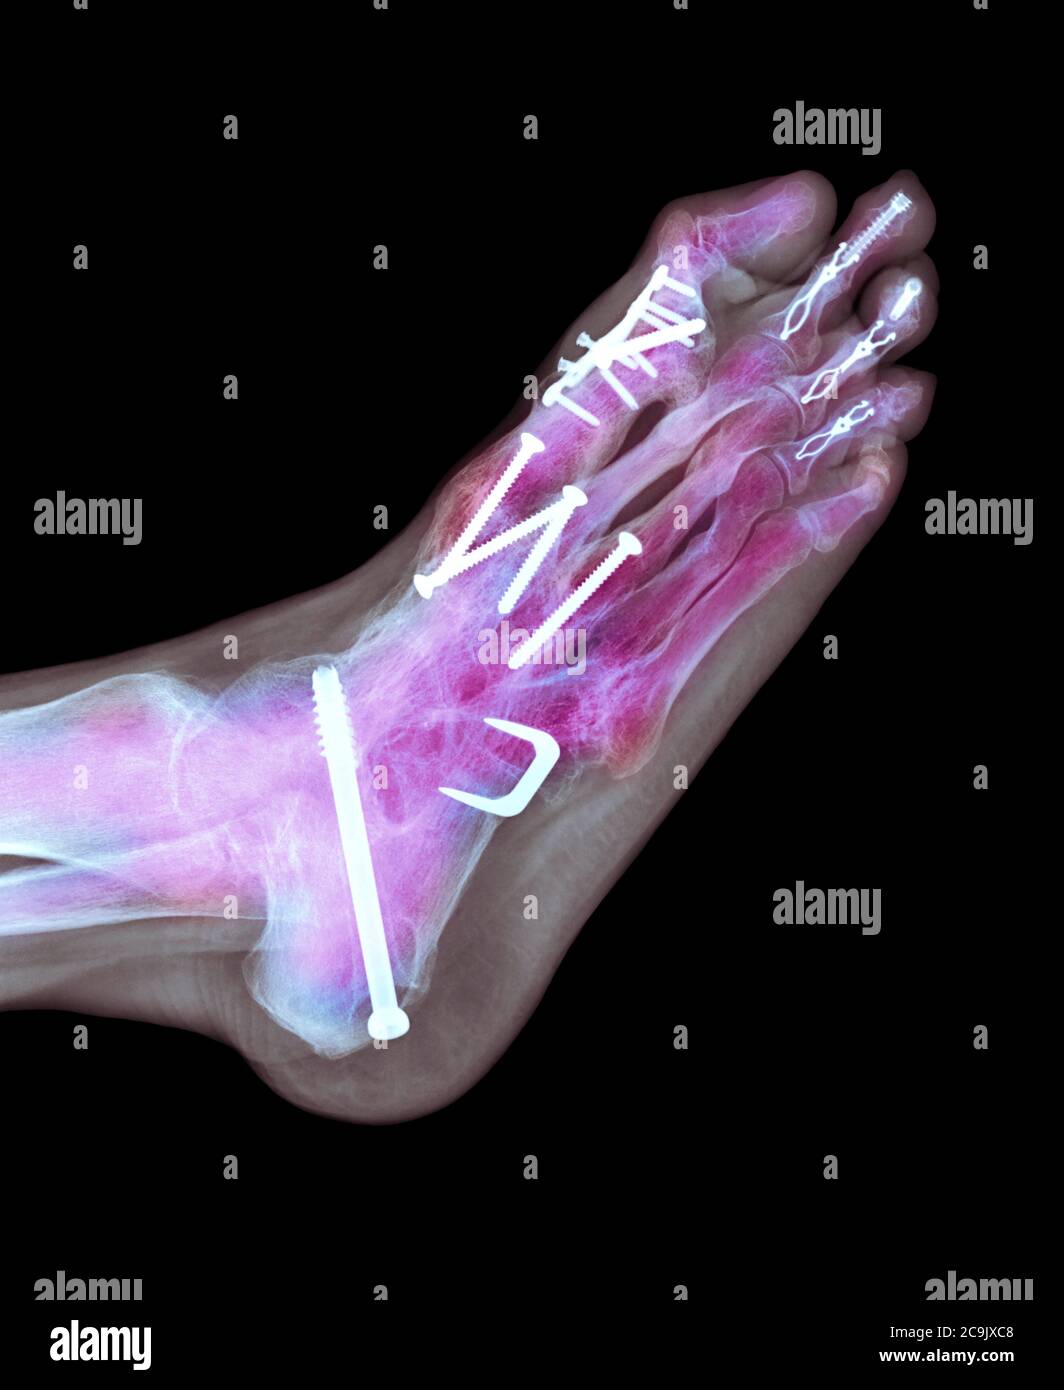

From www.alamy.com

Surgical fixation for rheumatoid arthritis of the feet. Coloured lateral Xray of screws and Surgery For Severe Foot Arthritis subtalar fusion is surgery to permanently join two bones in your foot so they become one. what is foot arthritis and how can you treat it? Full recovery can take 4 to 9 months, depending on the. foot surgery can be performed on the joint of the big toe, the joints in the middle of the foot,. Surgery For Severe Foot Arthritis.